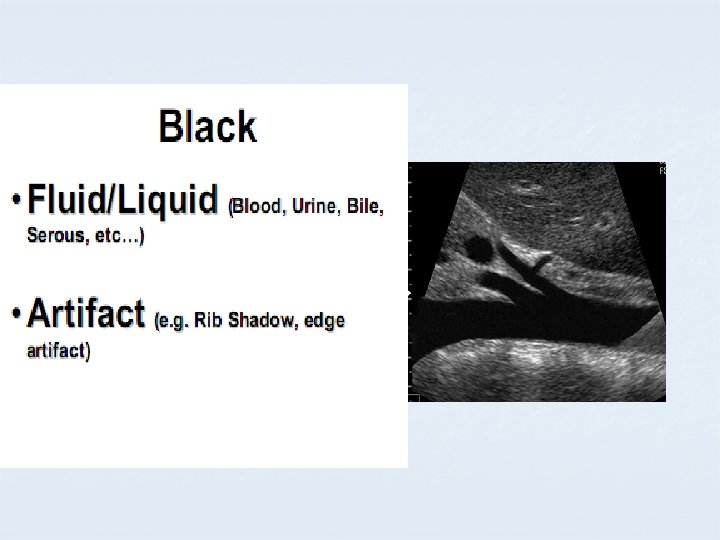

B MODE COLOURS BLACK ANECHOIC GREY HYPOECHOIC WHITE ECHOGENIC

APPEARANCE OF DIFFERENT TISSUES STRUCTURE APPEARANCE Viscera ; Liver Spleen Hypoechoic Muscles Hypoechoic with echogenic lines Blood, Urine, Bile, ascites, water Anechoic Bone, Stone Hyperechoic